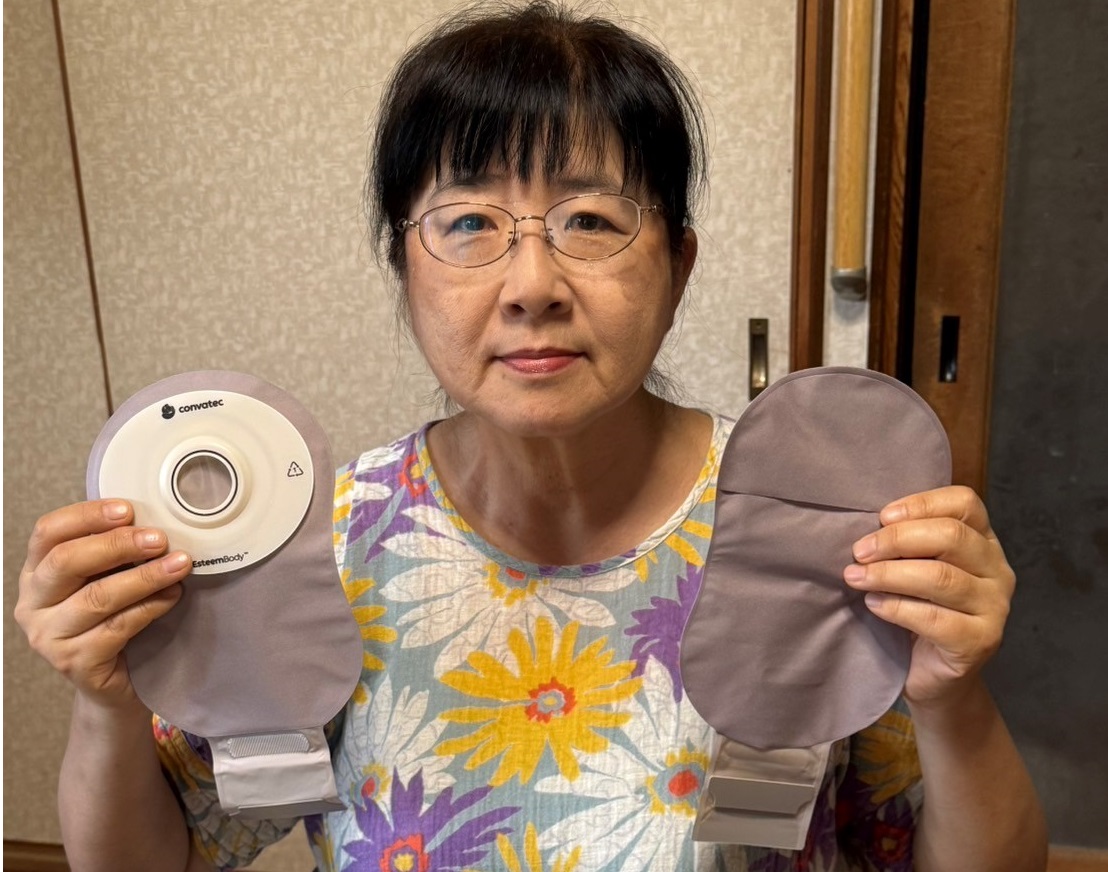

コンバテック新製品のストーマ装具エスティームボディ™ウロ(尿路用)を試していただき、同製品に切り替えたストーマ保有者の後藤安正先生*。今回は奥様にもご同席いただき、エスティ―ムボディ™ウロ(尿路用)に変えた決め手や同製品の感想についてお伺いしました。

最後に、ご同席いただいた奥様にも一言いただければと思います。一番近くで旦那様のことを見ていらっしゃると思いますが、エスティ―ムボディ™ウロを使い始めて、何か変化は感じることがありましたでしょうか?

奥様「夫もさきほど言っていましたが、やはり肌に触る部分が本当に気持ちいいらしいです。夫はとても汗かきなので、装具の袋が肌に触れる部分が蒸れてしまい、これまではパウチカバーが必須でした。エスティ―ムボディ™ウロだと速乾性があり、肌に袋があたる部分が蒸れないので、パウチカバーもつけずに過ごせているんです。見ていてすごいなと思いました。

奥様「あと、ストーマ装具を貼付する際に、私が正面から貼付位置を確認するサポートをするのですが、ビニールの透明の部分が前に使っていた装具よりかなりクリアで見やすくなったので助かっています。前のは、光が反射したりして、見えづらいことも多かったんです。」